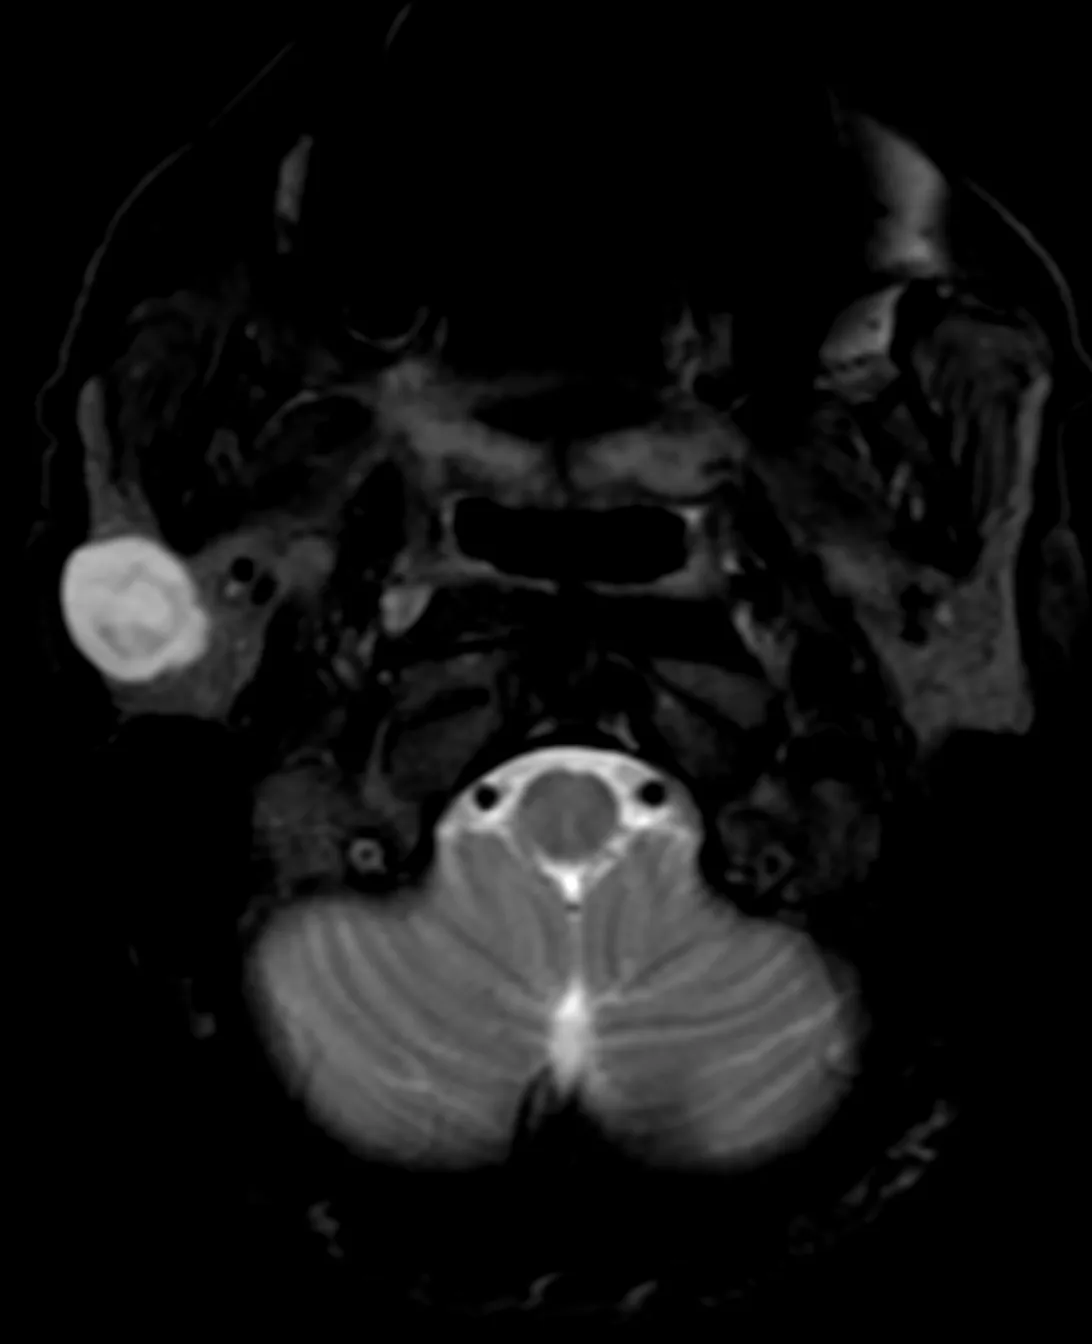

Небезосновательно предполагаемая шваннома заднего средостение у женщины 54 лет, обследованной не по её поводу. Бессимптомная, как и почти всегда.

Опухоли нервной системы чаще всего встречаются среди первичных новообразований средостения. Львиная доля их — доброкачественные. Шванномы — самые частые нейрогенный опухоли в грудной клетке, которые развиваются из шванновских клеток периферических нервов (причём, любых, вплоть до самых мелких и необязательно спинномозговых) и часто сидят в заднем средостении. Обнаруживаются почти всегда случайно при проведении различных методов визуализации.

Интраторакальная шваннома чаще всего расположена в заднем средостении. Это - медленно растущая доброкачественная опухоль с низкой вероятностью стать злокачественной. В крайне редких случаях злокачественной трансформации могут встречаться плеоморфные веретенообразные клетки и некротические и геморрагические изменения. Как и в данном случае, опухоль обнаруживается случайно при визуализации: эхокардиография, гастроэндоскопия, КТ или МРТ. Симптомы в подавляющем большинстве случаев, отсутствуют, но могут появиться, если опухоль начнет давить на окружающие органы.